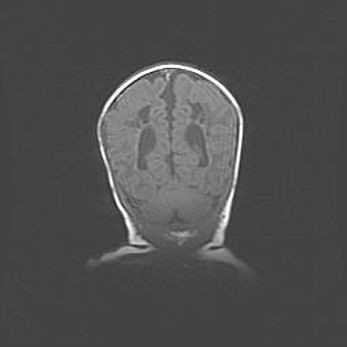

Церебральная ишемия II.

Возраст: 5 дней

Вес: 3400 г

Пол: женский

Окружность головы: 35 см

Срок гестации: 39 недель

Церебральная ишемия – это заболевание, характеризующееся недостаточностью (гипоксией) либо полным прекращением (аноксией) снабжения мозга кислородом по причине закупорки одного или нескольких сосудов. Это приводит к  что метаболическим расстройствам различной степени тяжести в тканях головного мозга, развитию коагуляционных некрозов и гибели нейронов.